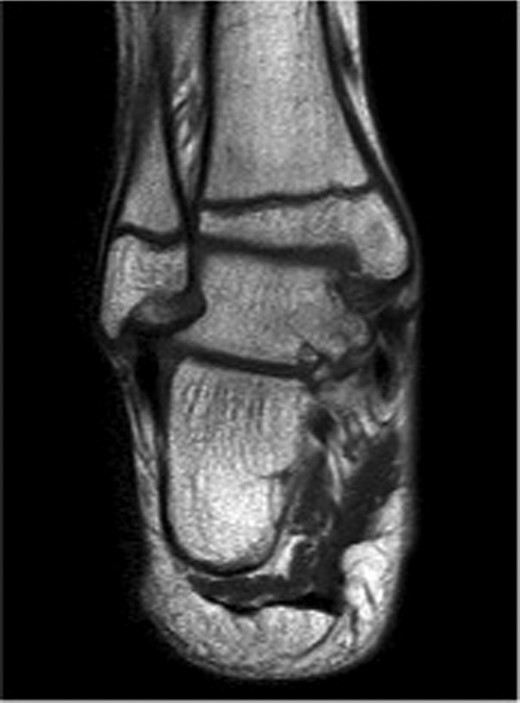

At 12 weeks follow-up, the patient was weight bearing comfortably with near full range of movement. A repeat CT and MRI scan showed no evidence of displacement of the fracture fragments with good evidence of talus fracture healing. MRI revealed reduction in bone marrow signal changes with no evidence of subchondral collapse (Figs 4 and 5).

12-week follow-up MRI scan confirms reduction in bone marrow oedema in injured medial tibio-talar joint.